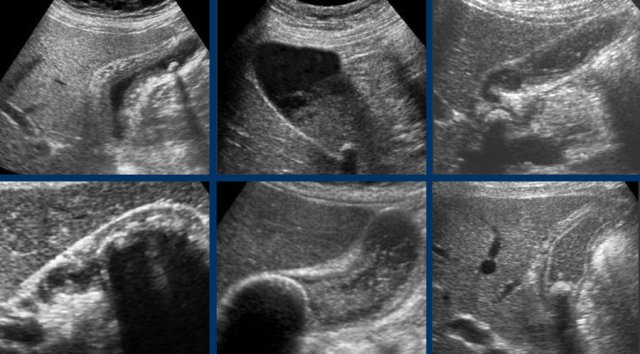

Silent witnesses of a biliary colic in six different patient.

US was done 6-12 hours after the pain episode.

All patients were symptom free at the moment of US.